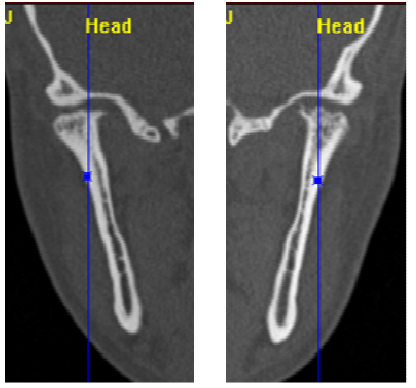

39.這張病人的CT scan顯示何處有骨折?

(A)右側顴骨骨體和左側下顎骨聯合 (B)右側上顎骨和左側下顎骨聯合 (C)左側顴骨骨體和右側下顎骨聯合 (D)左側上顎骨和右側下顎骨聯合